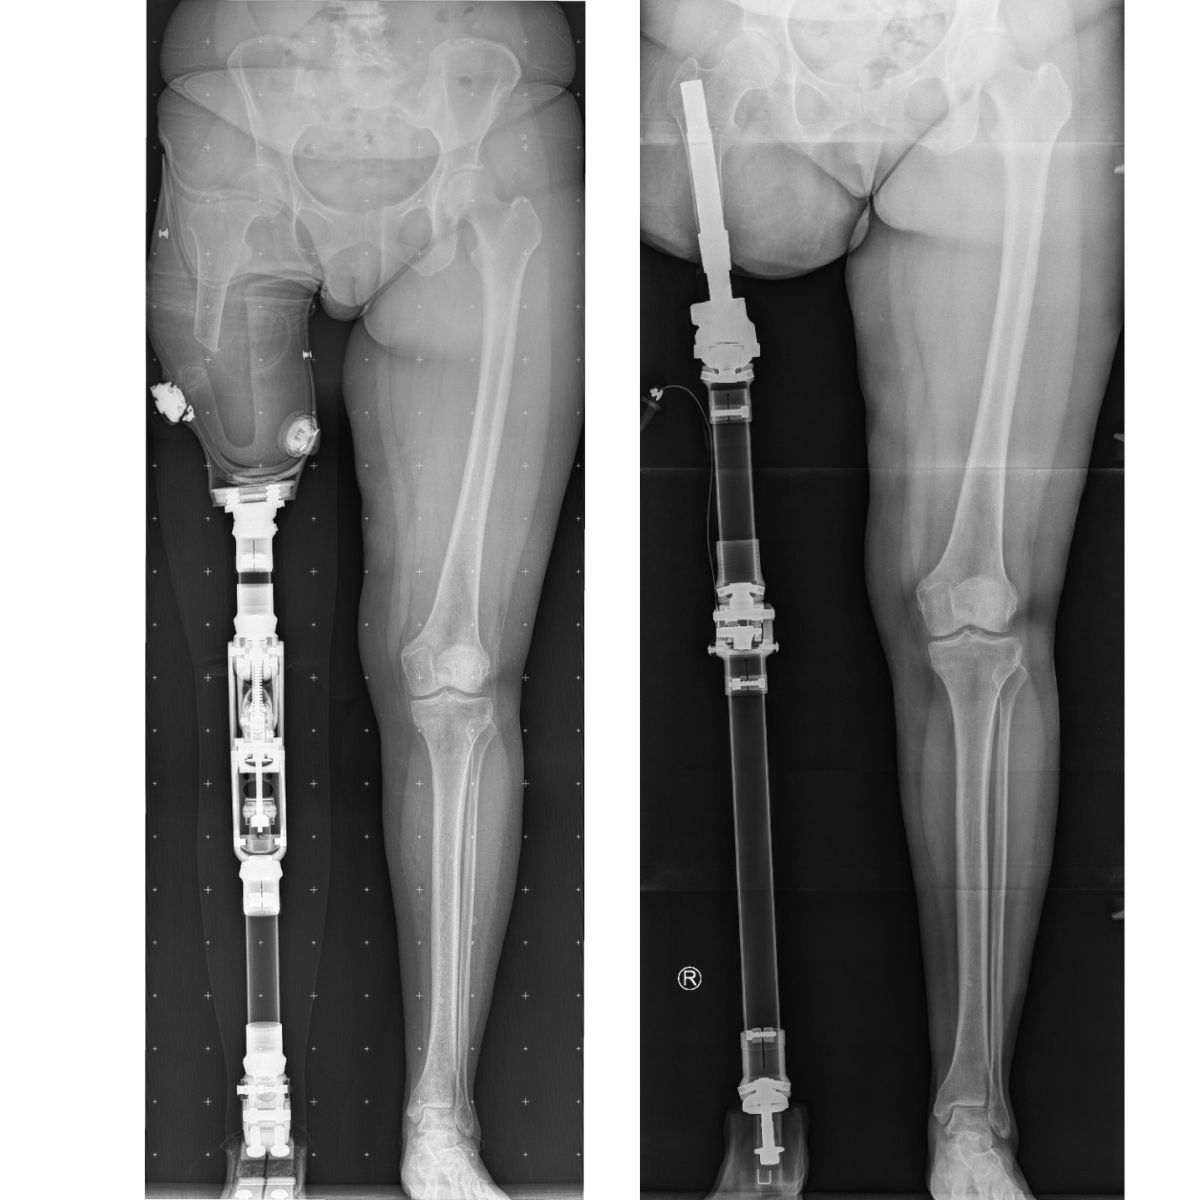

Osseointegracja to nowoczesna metoda rekonstrukcji, która eliminuje tradycyjny lej protezowy. Zamiast zakładać protezę na kikut, mocujesz ją bezpośrednio do implantu wszczepionego w Twoją kość. To rozwiązanie, które przywraca pacjentom po amputacji komfort życia, o jakim wcześniej mogli tylko marzyć

Tradycyjne rozwiązania protetyczne opierają się na bezpośrednim mocowaniu leja na skórze kikuta, który często bywa źródłem dyskomfortu, bolesnych otarć i nie zapewnia stabilności. Osseointegracja (z łac. os – kość,  integratio – łączenie) to przełomowa metoda, w której tytanowy implant trwale zrasta się z żywą tkanką kostną, stając się integralną częścią Twojego ciała.

W Paley European Institute stosujemy implant OPL (Osseointegrated Prosthetic Limb) – implant, który jako pierwszy na świecie był dedykowany do procedur jednoetapowych i jest udoskonalany od ponad 15 lat.

Zabieg polega na wprowadzeniu implantu do wnętrza kości i jego stabilnym osadzeniu oraz wyłonieniu łącznika przez skórę.

W procedurze jednoetapowej implantacja oraz wyprowadzenie łącznika następują podczas jednej operacji. W wybranych przypadkach stosowana jest procedura dwuetapowa.